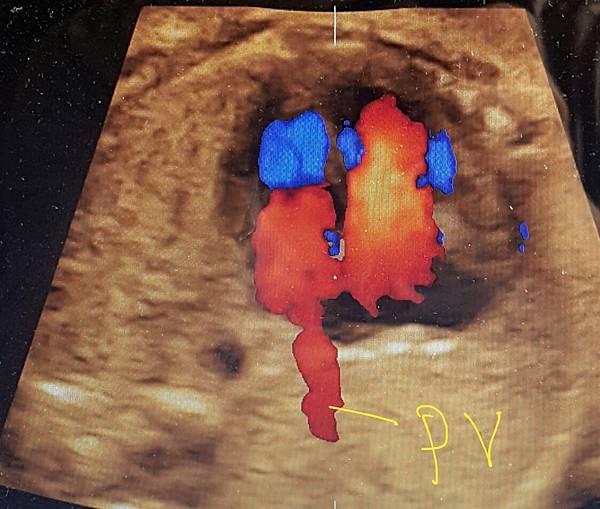

我看肺靜脈的心路歷程可以分成三個階段,第一個階段是用gray scale(黑白)看到左右肺靜脈下行支回到左心房(附圖 1.2.),第二個階段是用flow(彩色)看到左右肺靜脈回到左心房(附圖 3.4.),第三階段是同時要看到黑白和彩色的左右肺靜脈回到左心房,為什麼只有看flow(彩色)不安全呢?因為右肺靜脈的flow有時候是假影,為何會看到假影?因為右心房到左心房的flow overlapping(重疊)造成的(附圖 5.),如何判斷是假影,只要關掉flow看黑白的即可證明右肺靜脈沒有進入左心房(附圖 6.)。

如果同時看到左右肺靜脈進入左心房,這種誤判的機率下降很多,如果只能看到一條肺靜脈的血流,我會選擇左肺靜脈(附圖 7.8.),因為左肺靜脈的血流比較不會被overlapping,最安全的方法是黑白和彩色都看到左右肺靜脈進入左心房,只是需要胎兒姿勢配合,當然孕婦的體重也是需要考量的因素。